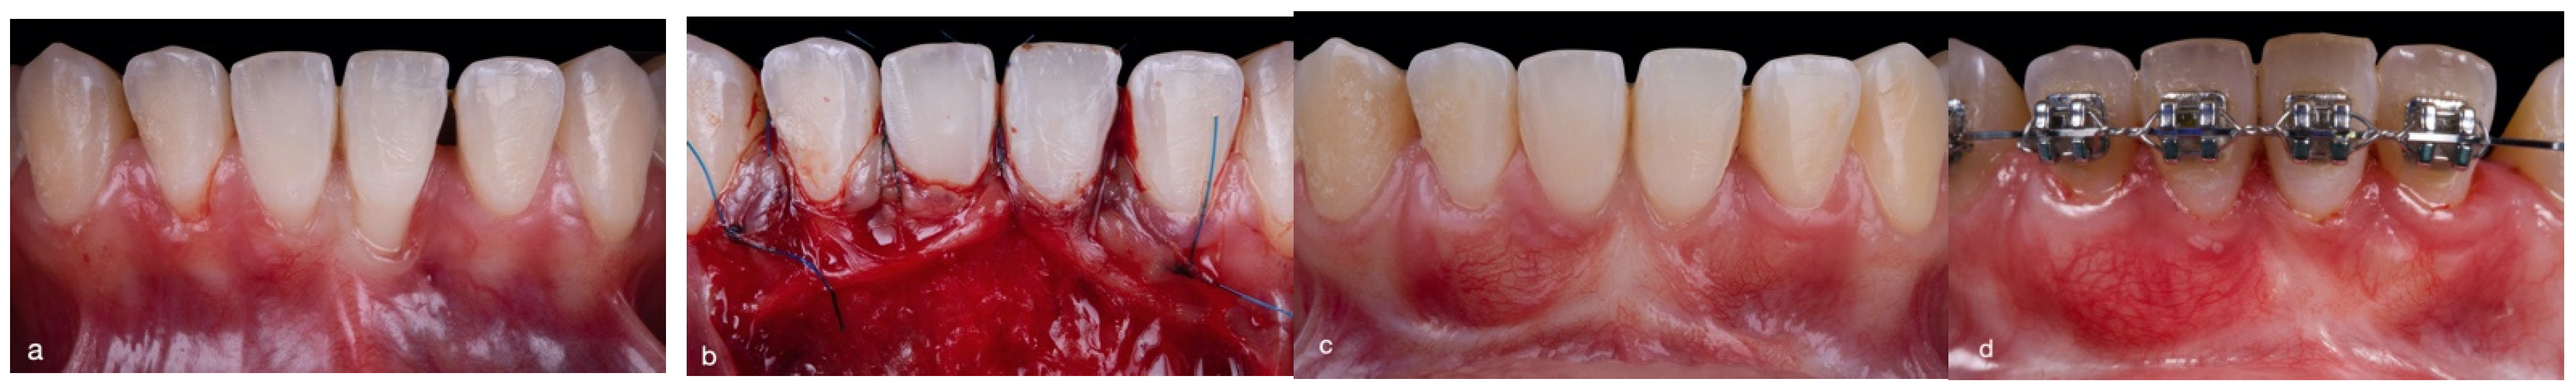

2.3. Surgical Approach